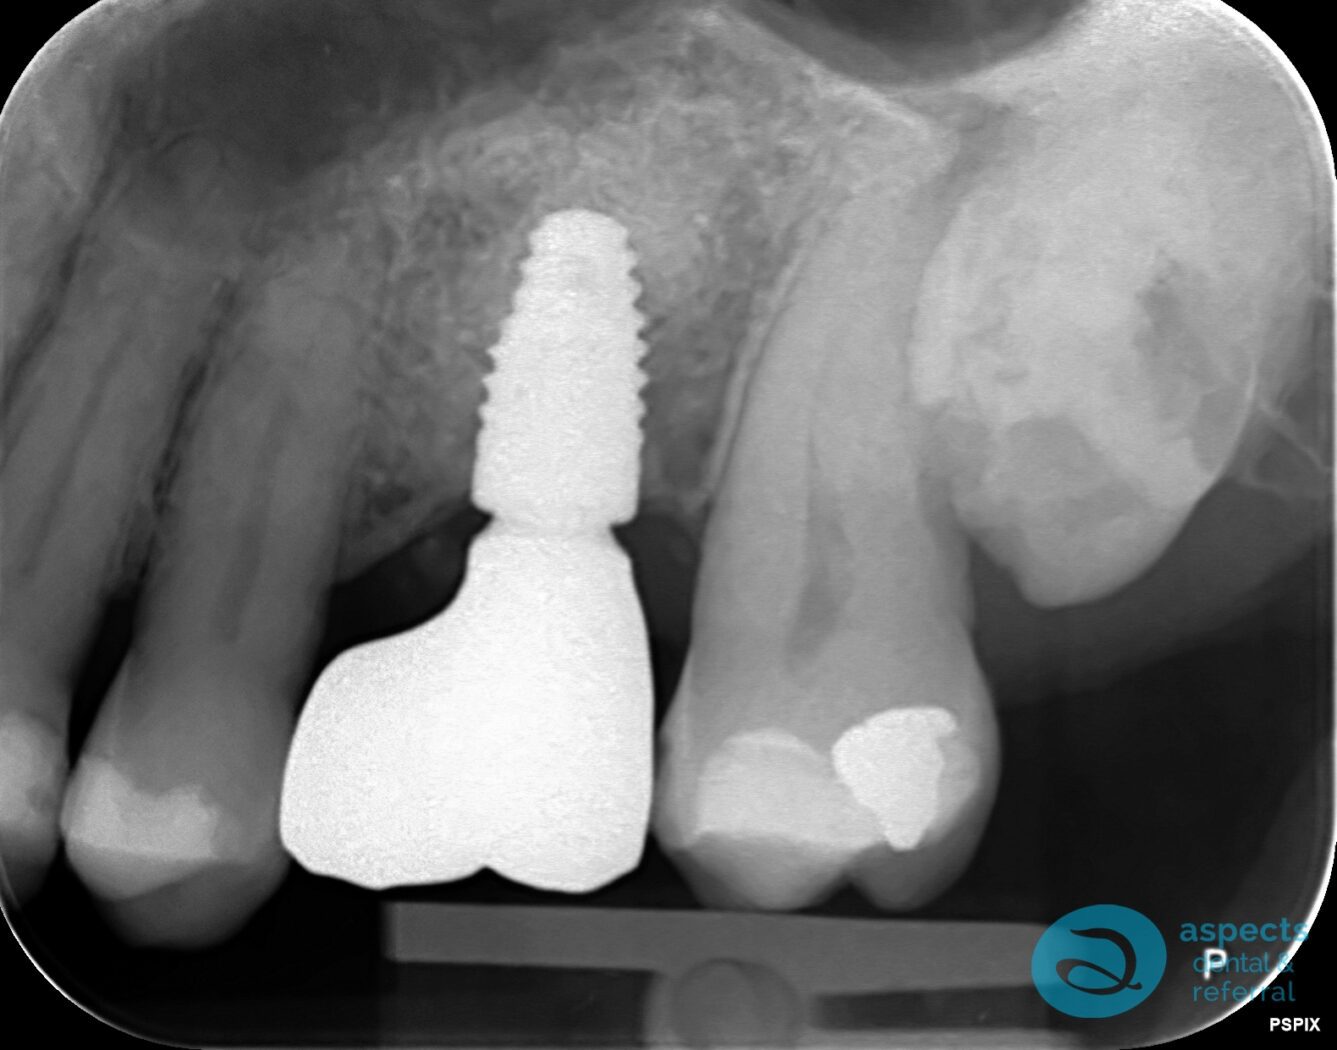

After Dental Implant & Bridge Xray

After an appropriate healing period, a postoperative radiograph confirmed successful integration of the graft and adequate bone volume. A dental implant was then placed in the grafted site without complications. Following osseointegration, an implant-retained Dental Bridge was fabricated and delivered to restore function and aesthetics.